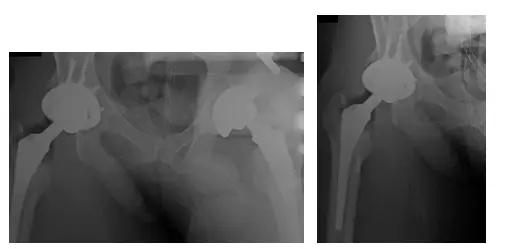

Cáscara acetabular

El cotilo acetabular encaja en la cavidad preparada en el acetábulo durante la intervención quirúrgica. El recubrimiento de plasma poroso favorece el crecimiento óseo y los tornillos sujetan el armazón.

La parte proximal del vástago femoral modular para la revisión de la prótesis de cadera

La parte proximal modular del vástago femoral en la imagen superior permite ajustar la anteversión intraoperatoriamente y acoplar un vástago largo.

Vástago distal de un componente femoral modular para prótesis de cadera de revisión

El vástago estriado largo encaja en la parte proximal del componente femoral modular. El vástago transmite la carga distalmente en el fémur y la forma estriada ofrece estabilidad rotacional.

Cabeza cerámica con manguito adaptador

Para las cirugías de sustitución pueden utilizarse cabezas de cerámica o de aleación metálica.